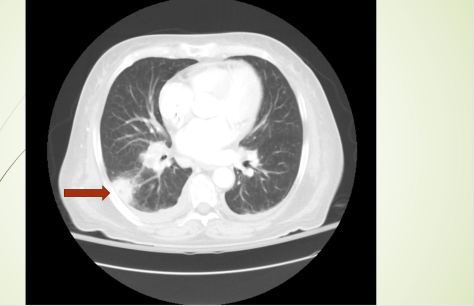

Today Narges presented a case with an elderly, immunocompromised patient with recent travel to Southern California, presenting with several weeks history of cough, night sweats, and generalized malaise, found to have a cavitary lesion in the RLL of the lung. Biopsy revealed C. immitis!